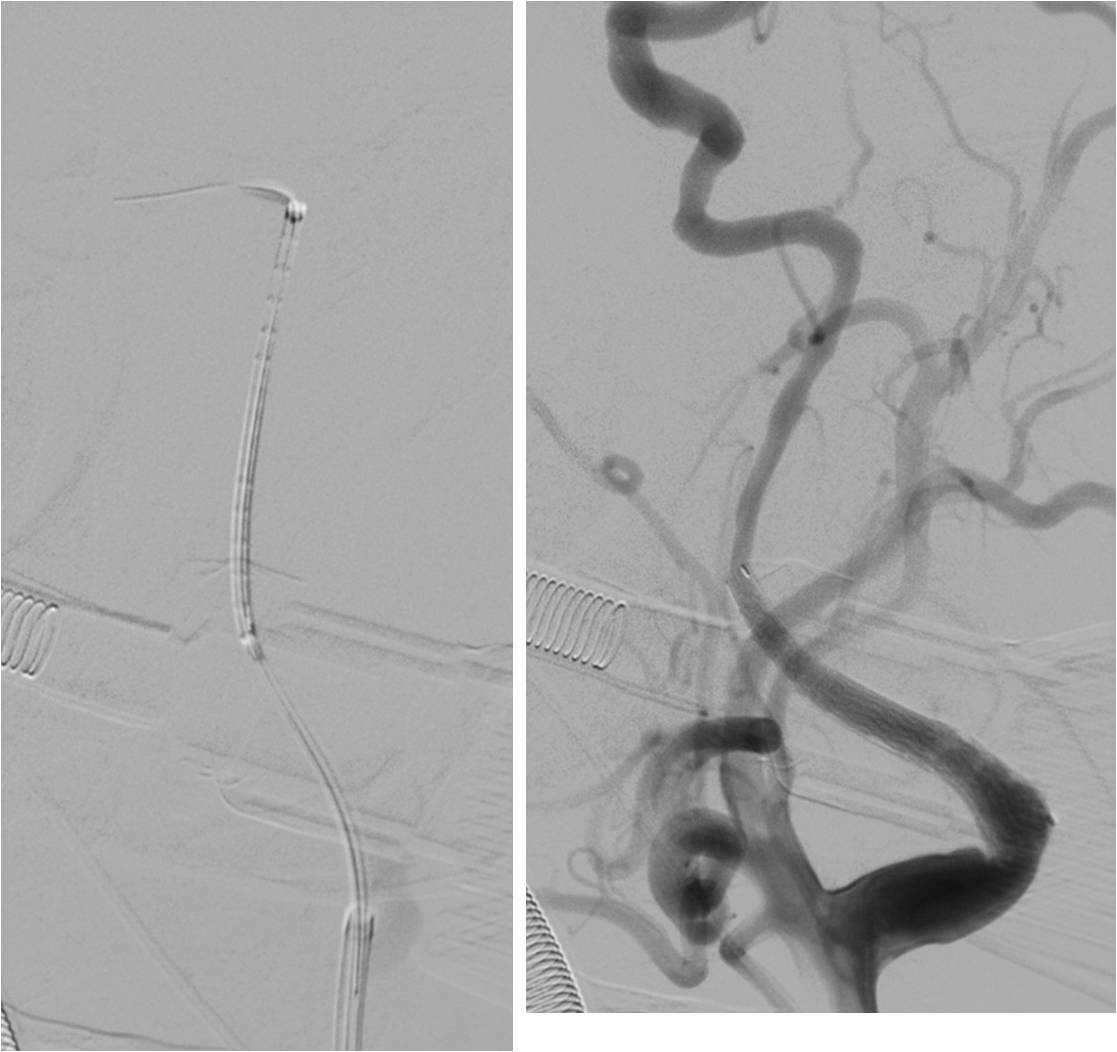

》全麻下手术

》术后C臂CT无出血

》术后20小时复查头颅CT无出血。

静脉溶栓后,血管内治疗球囊扩张或植入支架:

不用抗血小板药物是否可行?